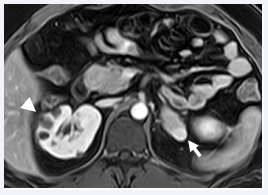

US, CT and MRI play a pivotal role in the diagnosis, characterization, and screening of renal lesions in VHL disease. US helps in differentiating cystic from solid masses and has the advantage of avoiding ionizing radiation, given the fact that these patients require frequent surveillance scans. CT and MRI are very sensitive for cysts or masses smaller than 2 cm. At CT/MRI, bilateral kidneys demonstrate multiple simple and complex cysts, cystic masses with enhancing, solid components, and solid masses of varying sizes with heterogeneous contrast enhancement (Figure 5) [5,22].

Multiple renal cysts and renal cell carcinoma in a 33-yearold man, who came to emergency room with hematuria. There was no family history of von Hippel-Lindau disease. Coronal T2- weighted (A) and contrast-enhanced T1- weighted MR images show multiple simple and complex cysts involving bilateral kidneys (arrows) and a large heterogenously enhancing renal mass in the right kidney (arrowhead) consistent with renal cell carcinoma. Additionally, multiple simple pancreatic cysts are also identified (not shown here). Based on these findings, the possibility of VHL disease was suspected, which was proved subsequently by genetic testing.

Figure 5: Multiple renal cysts and renal cell carcinoma in a 33-yearold man, who came to emergency room with hematuria. There was no family history of von Hippel-Lindau disease. Coronal T2- weighted (A) and contrast-enhanced T1- weighted MR images show multiple simple and complex cysts involving bilateral kidneys (arrows) and a large heterogenously enhancing renal mass in the right kidney (arrowhead) consistent with renal cell carcinoma. Additionally, multiple simple pancreatic cysts are also identified (not shown here). Based on these findings, the possibility of VHL disease was suspected, which was proved subsequently by genetic testing.

MRI eliminates ionizing radiation and is preferred in young patients and on those with renal failure. Complex cysts and solid masses enhance on postcontrast T1-weighted images and sometimes may show a hypointense pseudocapsule on T2-weighted images [23,24]. The preferred treatment in renal cell carcinoma associated with VHL disease is nephron-sparing procedure (either partial nephrectomy or image-guided ablation). Due to the high probability of appearance of new renal neoplastic lesions; lesions greater than 3 cm undergo treatment whereas smaller lesions are followed-up at close intervals [8,18]. The natural history of cysts is variable; some may involute leaving small scars while in others the solid component may enlarge. Complex cysts are precursors to renal cell carcinoma and require close follow-up [18]. Screening protocol for renal cysts/masses in VHL includes annual abdominal US examination from the age of 10 years followed-up with CT or MRI studies depending on the US findings or direct annual CT or MRI studies bypassing US [1,5].